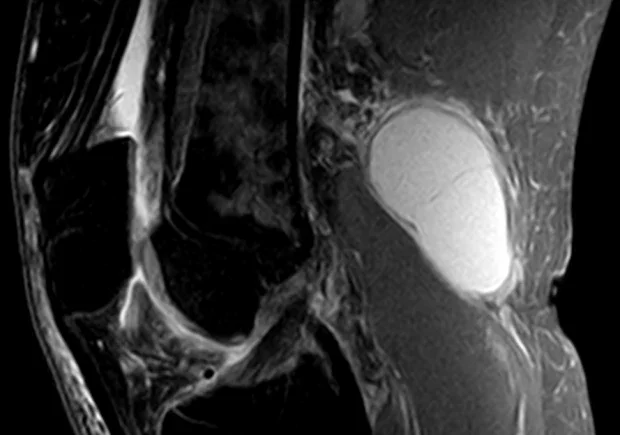

Изображение: Hellerhoff, CC BY-SA 3.0, via Wikimedia Commons

Златният стандарт за диагностициране на кисти на Бейкър и диференцирането им от други състояния е ядрено-магнитния резонанс (ЯМР). Той позволява оценка на аномалии на меките тъкани и има допълнителното предимство, като помага за откриването на свързани ставни заболявания. Така чрез него е възможно да се направи много по-точна оценка на целият спектър от свързани заболявания.